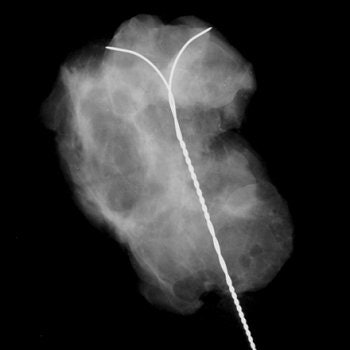

| Ductal carcinoma in situ in left breast of 44-year-old woman. Oblique view mammogram and mammographic magnification view of surgical specimen shows cluster of punctate calcifications (arrow) close to hookwire. |

| Same patient as above. The MR study (axial plane) does not show any foci of enhancement. Bazzocchi M, Zuiani C, Panizza P, Del Frate C, Soldano F, Isola M, Sardanelli F, Giuseppetti GM, Simonetti G, Lattanzio V, Del Maschio A, "Contrast-Enhanced Breast MRI in Patients with Suspicious Microcalcifications on Mammography: Results of a Multicenter Trial" (AJR 2006; 186:1723-1732). |

Overall, the sensitivity of MRI was 87%, the specificity was 68%, the positive predictive value was 84%, the negative predictive value was 71%, and the accuracy was 80%.

"The not-perfect sensitivity of MRI -- 87% -- is a crucial point that prevents us from clinical use of MRI in the diagnosis of mammographically detected microcalcifications," the group wrote. "MRI cannot replace percutaneous or surgical biopsy, which gives pathological information."